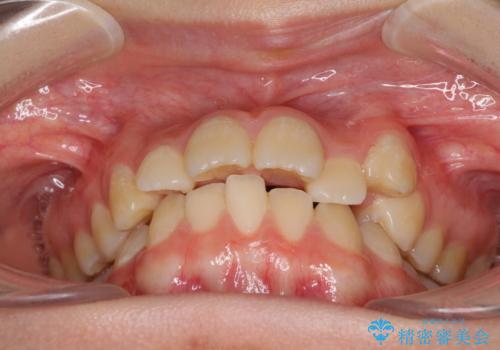

- 目立つ八重歯を改善したいとのことで来院された患者様です。

奥歯の咬み合わせは左右とも理想的なものでしたが、下顎前歯が1本欠損しているため、上下のバランスを保つことが難しい歯列でした。

唇を閉じたときに上顎前歯が下顎の唇に乗っかる印象があったため、八重歯の後方にある小臼歯を1本抜歯することとしました。

まずは補助装置を用いて八重歯を改善し、インビザラインにて歯列を整えましたが、当初の懸念が的中し、臼歯部の咬合を安定させることができませんでした。

海外留学の予定もあったため、後半は上下ワイヤー装置にて矯正治療を継続し、違和感なく咬合させることとなりました。